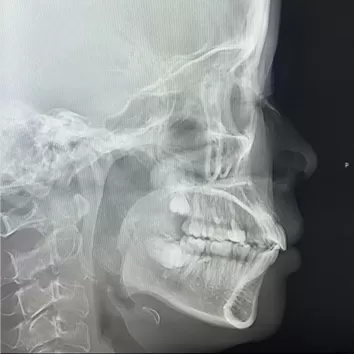

Rayons X avant le traitement

[Radiographie panoramique/Céphalogramme latéral]